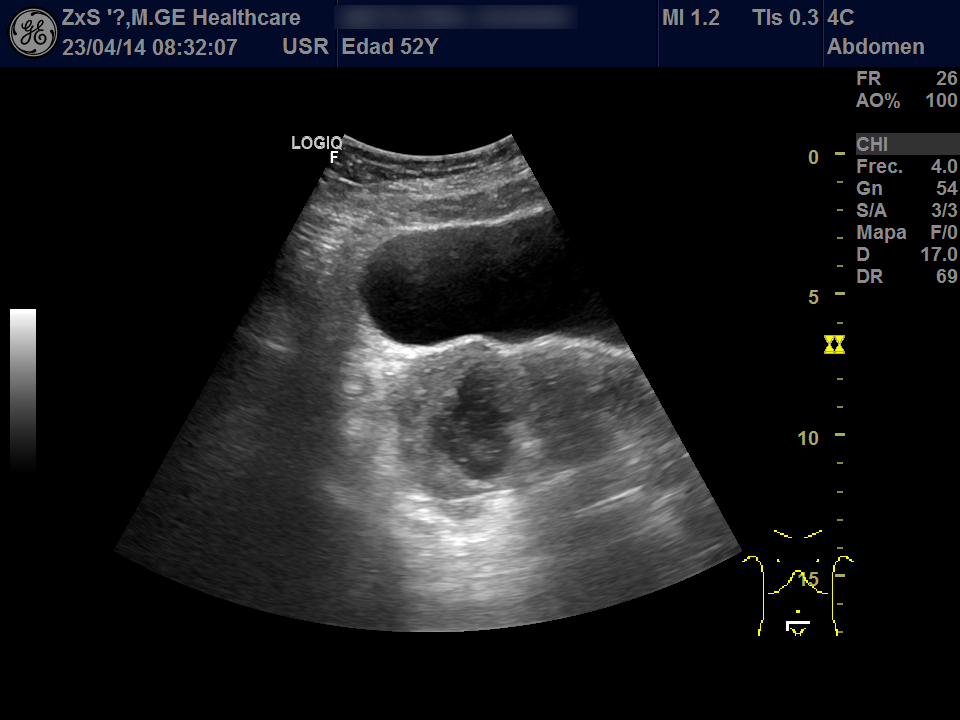

Hígado de bordes lisos y ángulo agudo, aspecto heterogéneo, no se observan LOES. Vía biliar extra e intrahepática no dilatada. Vesícula poco replecionada sin imágenes en su interior, Murphy ecográfico negativo. Ambos riñones de localización y tamaño normal. Buena diferenciación córtico-sinusal y en riñón derecho discreto aumento del tamaño de la pelvis renal compatible con hidronefrosis grado 2. Vejiga bien replecionada sin ecos en su interior. Se objetiva útero de tamaño normal con una imagen hiperecogénica que corresponde a DIU y en la zona derecha una lesión redondeada de aproximadamente 5,5 x 6,5 de diámetro de contenido heterogéneo que dudamos si puede corresponder a masa ovárica desconocida. Se deriva al hospital por sospecha de masa ovárica.

Evolución y seguimiento: Urgencias hospital TAC abdominal: en región anexial lesión de aspecto sólido-quístico de 6,5 x 5,5 cm con cambios inflamatorios de la grasa adyacente y que produce leve desplazamiento del útero hacia la izda. No se observan colecciones, neumoperitoneo, ni líquido libre intraabdominal.